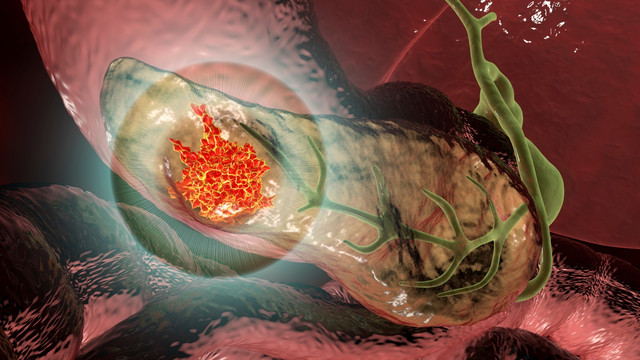

Βρέθηκε θεραπεία για τον καρκίνο του παγκρέατος; Τι πρέπει να γνωρίζετε για τη νέα σπουδαία ανακάλυψη

Ο καρκίνος του παγκρέατος θεωρείται ένας από τους πιο επιθετικούς. Ένας βασικός λόγος είναι ότι ο όγκος αναπτύσσει πολύ γρήγορα αντοχή στις διαθέσιμες θεραπείες. Ωστόσο, μια νέα μελέτη από το Spanish National Cancer Research Centre (CNIO) αναπτερώνει τις ελπίδες για την αντιμετώπισή του, καθώς διαπιστώθηκε πως με την εφαρμογή μιας τριπλής συνδυαστικής θεραπείας εξαλείφθηκαν παγκρεατικοί όγκοι σε πειραματόζωα και απετράπη η επανεμφάνισή τους.

Τα ευρήματα, που δημοσιεύθηκαν στο επιστημονικό περιοδικό PNAS, δείχνουν ότι η ταυτόχρονη στόχευση τριών κρίσιμων σημείων της μοριακής οδού του ογκογονιδίου KRAS οδηγεί σε μακροχρόνια υποχώρηση των όγκων.

Το κλειδί της ανακάλυψης βρίσκεται στην αποφυγή της αντοχής που εμφανίζεται όταν το ογκογονίδιο μπλοκάρεται σε ένα μόνο σημείο. Η ομάδα του CNIO συνδύασε έναν πειραματικό αναστολέα KRAS, ένα φάρμακο που έχει ήδη εγκριθεί για τον καρκίνο του πνεύμονα και έναν αποικοδομητή πρωτεϊνών. Το αποτέλεσμα ήταν η εξαφάνιση των όγκων χωρίς σημαντικές παρενέργειες σε τρία διαφορετικά ζωικά μοντέλα.